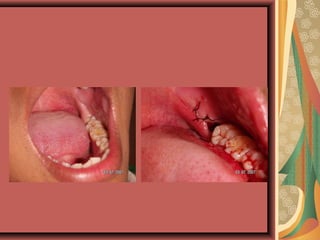

Prevention of pericoronitis

trismus, cellulitis

Prevention of infection , such tooth will be

problematic under the denture